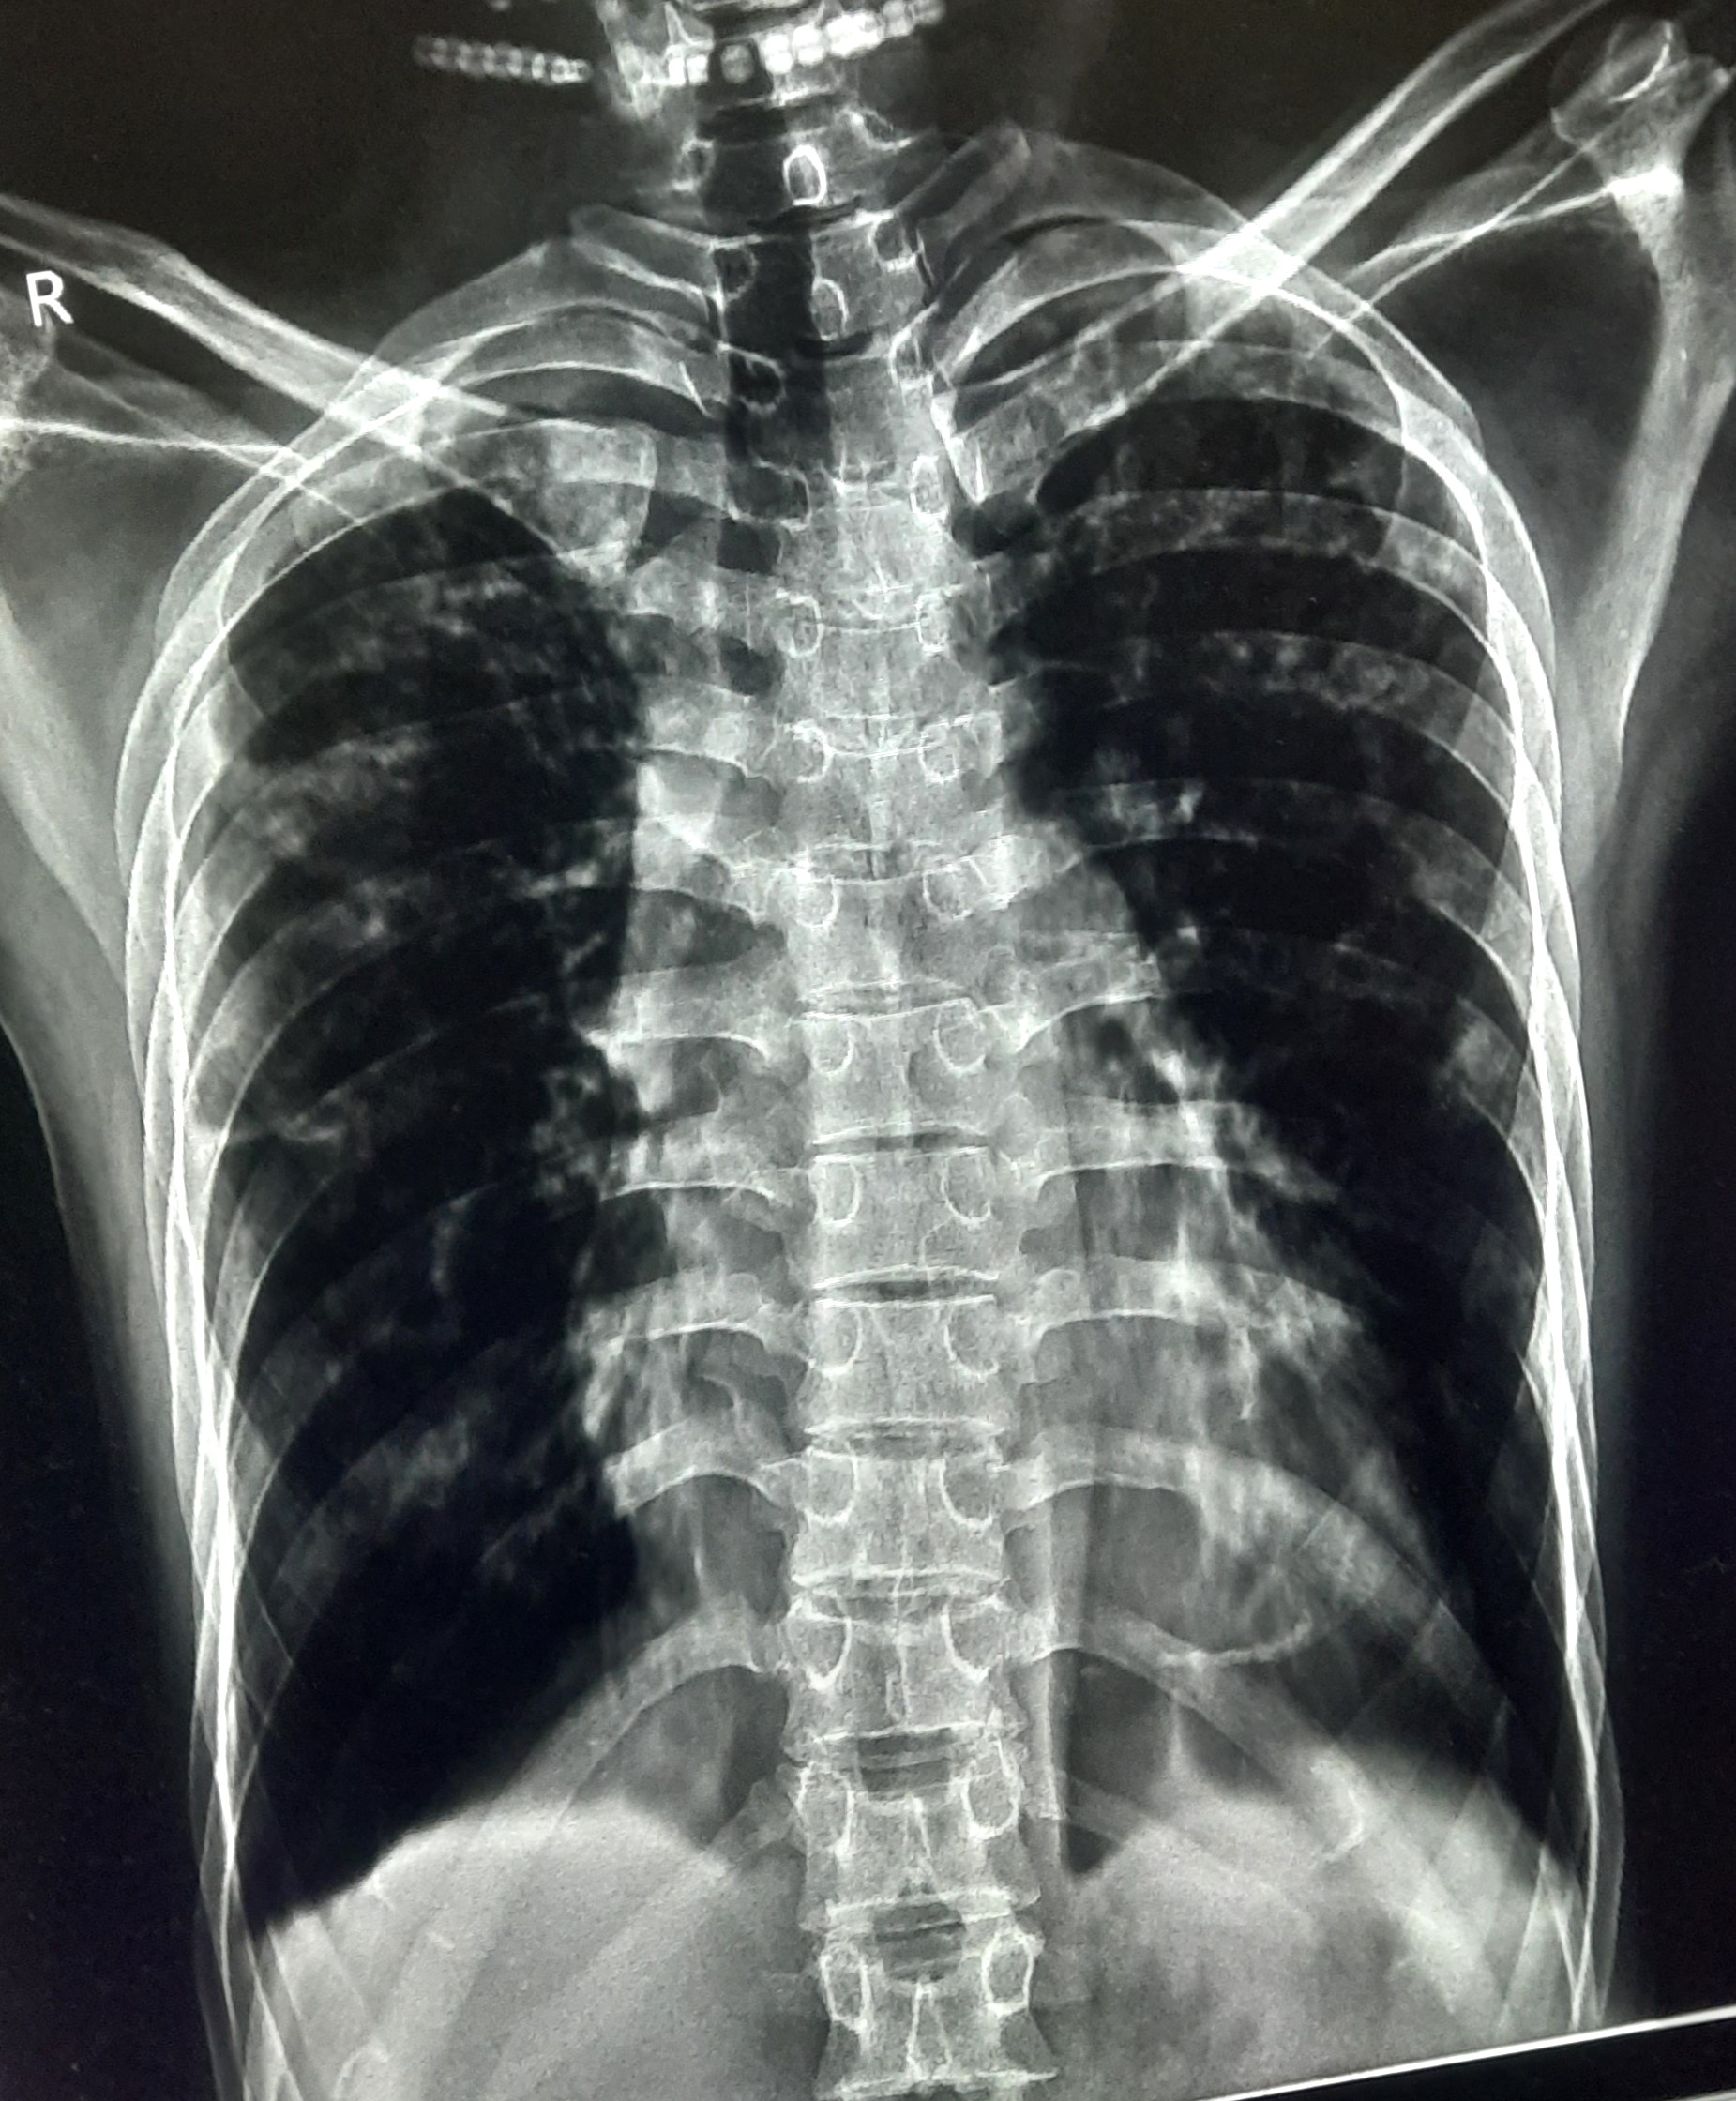

| 51 | IGGMC, Nagpur, Nagpur | P2 | 29-4421 | Santosh Neware | Consent taken on Paper | 40 Yrs. |

Provisional Diag : Pulmonary Tuberculosis

Final Diag : Pulmonary tuberculosis (Microbiologically Confirmed PTB) |

TB Case (Confirmed) | Right Upper & mid zone fibro cavitary lesion present, upward pull of right hemidiaphragm, tracheal pull right sided | Abnormality visible on x-ray |